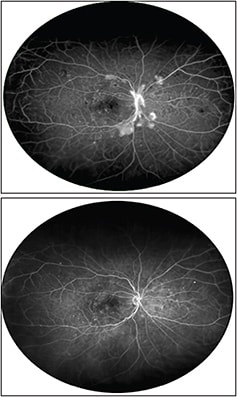

Figure 3. (Top) Optos UWF image of a patient with proliferative diabetic retinopathy. In addition to the optic nerve neovascularization, areas of neovascularization are noted along the superior and inferior arcades, both temporally and nasally. Peripheral ischemia is also noted. UWF imaging is essential to capture the extent of retinopathy completely. (Bottom) Optos UWF image of the same patient following three intravitreal anti-VEGF injections. There are complete regression of the neovascularization and considerable improvement in the peripheral ischemia. However, microvasular abnormalities are still present posteriorly and in the peripheral retina. UWF imaging is useful for following the treatment response to intravitreal injections.